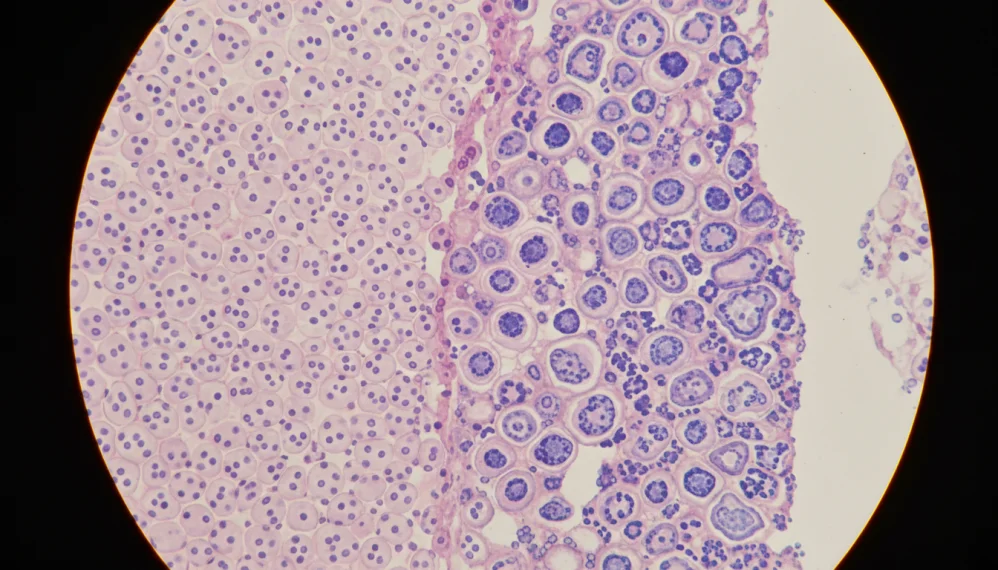

Colposcopia este o metoda optica de examinare a vaginului, a vulvei si a colului uterin cu ajutorul colposcopului. Colposcopia este cea mai buna metoda de a diagnostica fazele preliminare ale acestei boli, facandu-se in acelasi timp probe la tesuturile moi. Este o metoda care se foloseste in special la femei.

Biopsie (Luarea de probe din tesuturile moi)

Daca se descopera la colposcopie o anormalitate a tesuturilor moi, se va efectua o biopsie la orificiul uterin (colul uterin) pentru a clarifica situatia. Proba se va lua din tesutul cel mai afectat. Biopsia se face cu instrumente speciale. Proba de tesut este aproximativ 2x2mm. Biopsia nu este dureroasa.